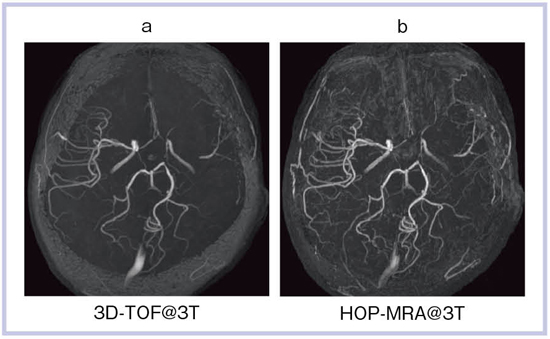

パーティを彩るご馳走や 次世代のOpen Bore 3T MRIによる臨床応用 3T MRIの臨床応用 健康/医学の詳細情報

次世代のOpen Bore 3T MRIによる臨床応用 3T MRIの臨床応用。Look back Gyro cup ②「 CSF Flow with Low RFA SSTSE。次世代のOpen Bore 3T MRIによる臨床応用 3T MRIの臨床応用。